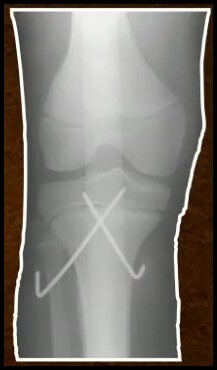

7

Q

FX Diafisária do Fêmur

TTO 6 - 10 anos?

A

HASTES FLEXÍVEIS

ou

Placa (>50 Kg)

Fixador Externo (Cominuição)